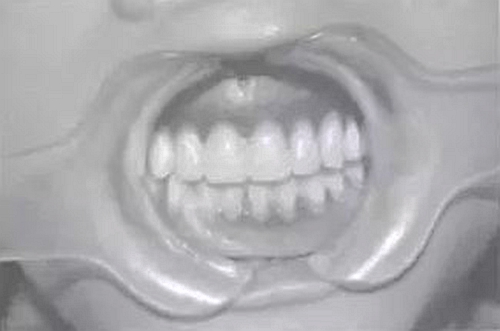

預(yù)約定時(shí)復(fù)診。完成修復(fù)后,囑患者注意合理飲食及口腔衛(wèi)生,每年復(fù)診。隨訪4年,患者自覺(jué)良好,飲食咀嚼正常,復(fù)查:臨床檢查見(jiàn),16、17、26、36、46、75、85合面見(jiàn)充填體,26遠(yuǎn)中面缺損平齦緣,17臨床牙冠已完全暴露于口內(nèi),27可見(jiàn)1/3牙冠:義齒就位后其固位及穩(wěn)定性較好、無(wú)壓痛、患者發(fā)音正常、進(jìn)食正常:X線片示:75、85牙根可見(jiàn)根尖1/3處發(fā)生吸收、17、27牙根未發(fā)育完全;牙槽骨未發(fā)現(xiàn)吸收情況;同4年前相較而言,戴用義齒后,牙槽骨可見(jiàn)輕微增長(zhǎng)。

圖3修復(fù)后口內(nèi)像